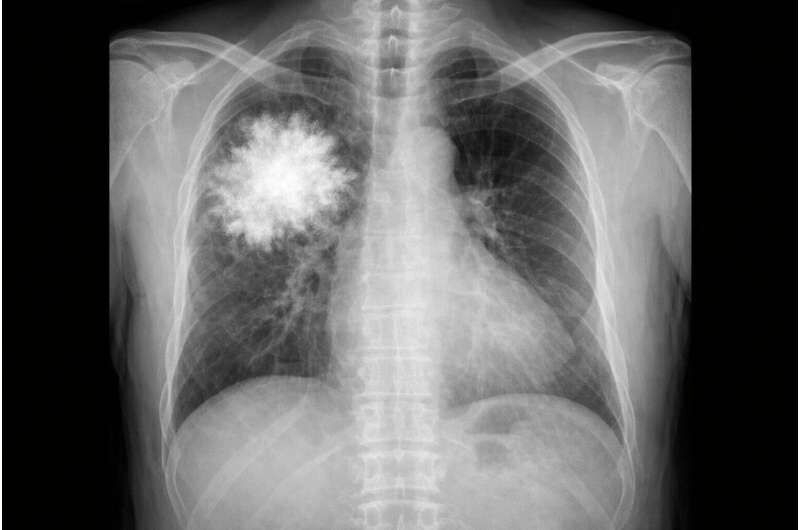

گروه پژوهشی یک قدم فراتر رفت و یک مدل فقط متنی (بدون دسترسی به دادههای بصری) را برای پاسخ به سؤالات مربوط به عکسهای قفسه سینه آموزش داد.

نتیجه شگفتآور بود: این مدل متنی در یک آزمون استاندارد تفسیر عکس قفسه سینه، هم از سامانههای پیشرفته هوش مصنوعی و هم از پزشکان انسانی بهتر عمل کرد.